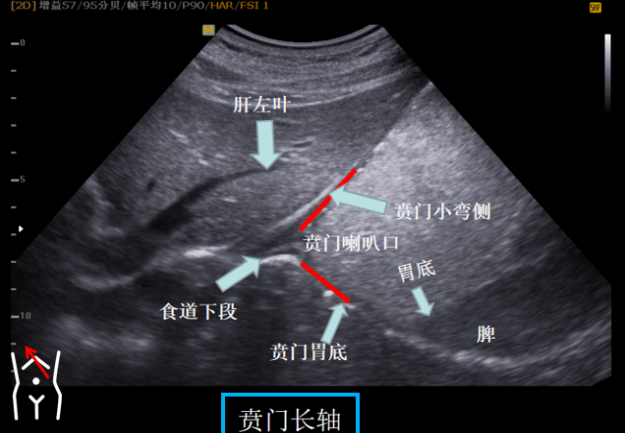

第一组贲门切面

受检者平卧位我们将探头置放剑突区以肝左叶及腹主动脉作为寻找贲门的界面原位旋转探头找到食道下段及与贲门连接处轻摆探头将贲门喇叭口清晰显示再将探头向左上翘此时胃底部也可以显示所以第一组切面我们称之为主看贲门附看胃底。